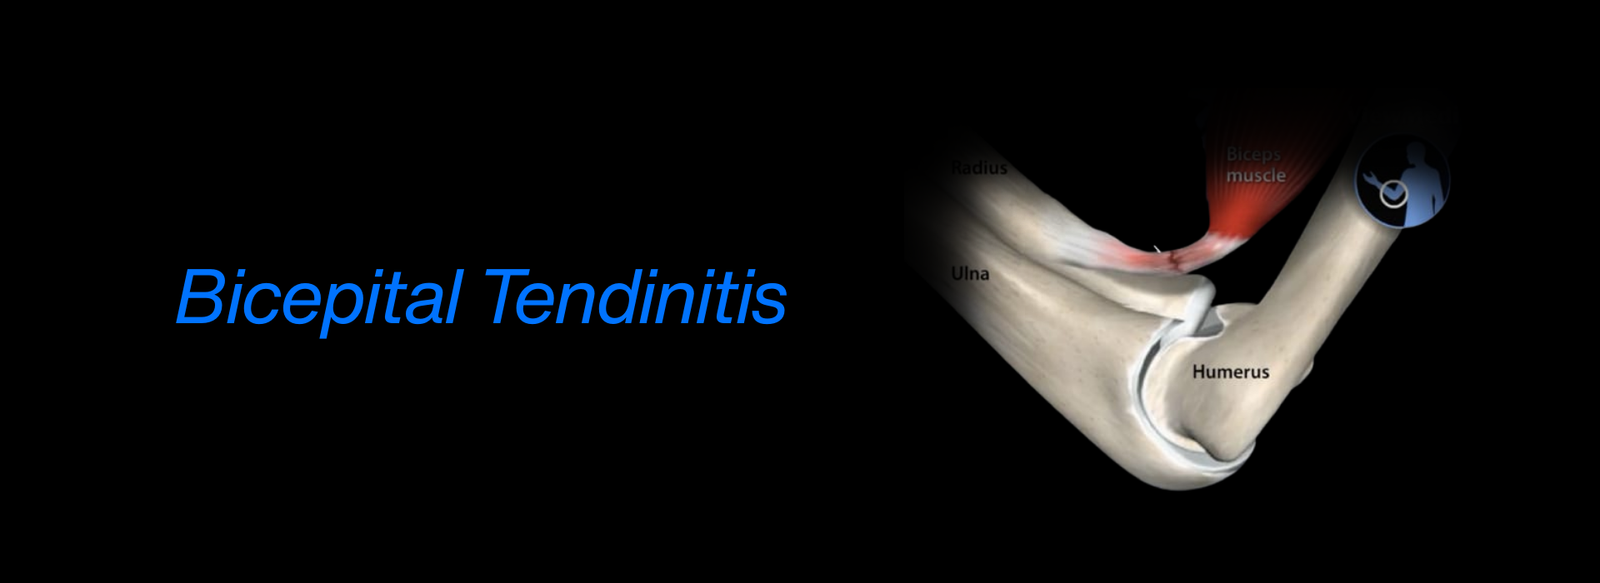

Fellowship in Arthroscopy: Expertise in minimally invasive surgery to diagnose and treat joint conditions, such as torn cartilage or ligament injuries, particularly of the knee, shoulder, and hip.